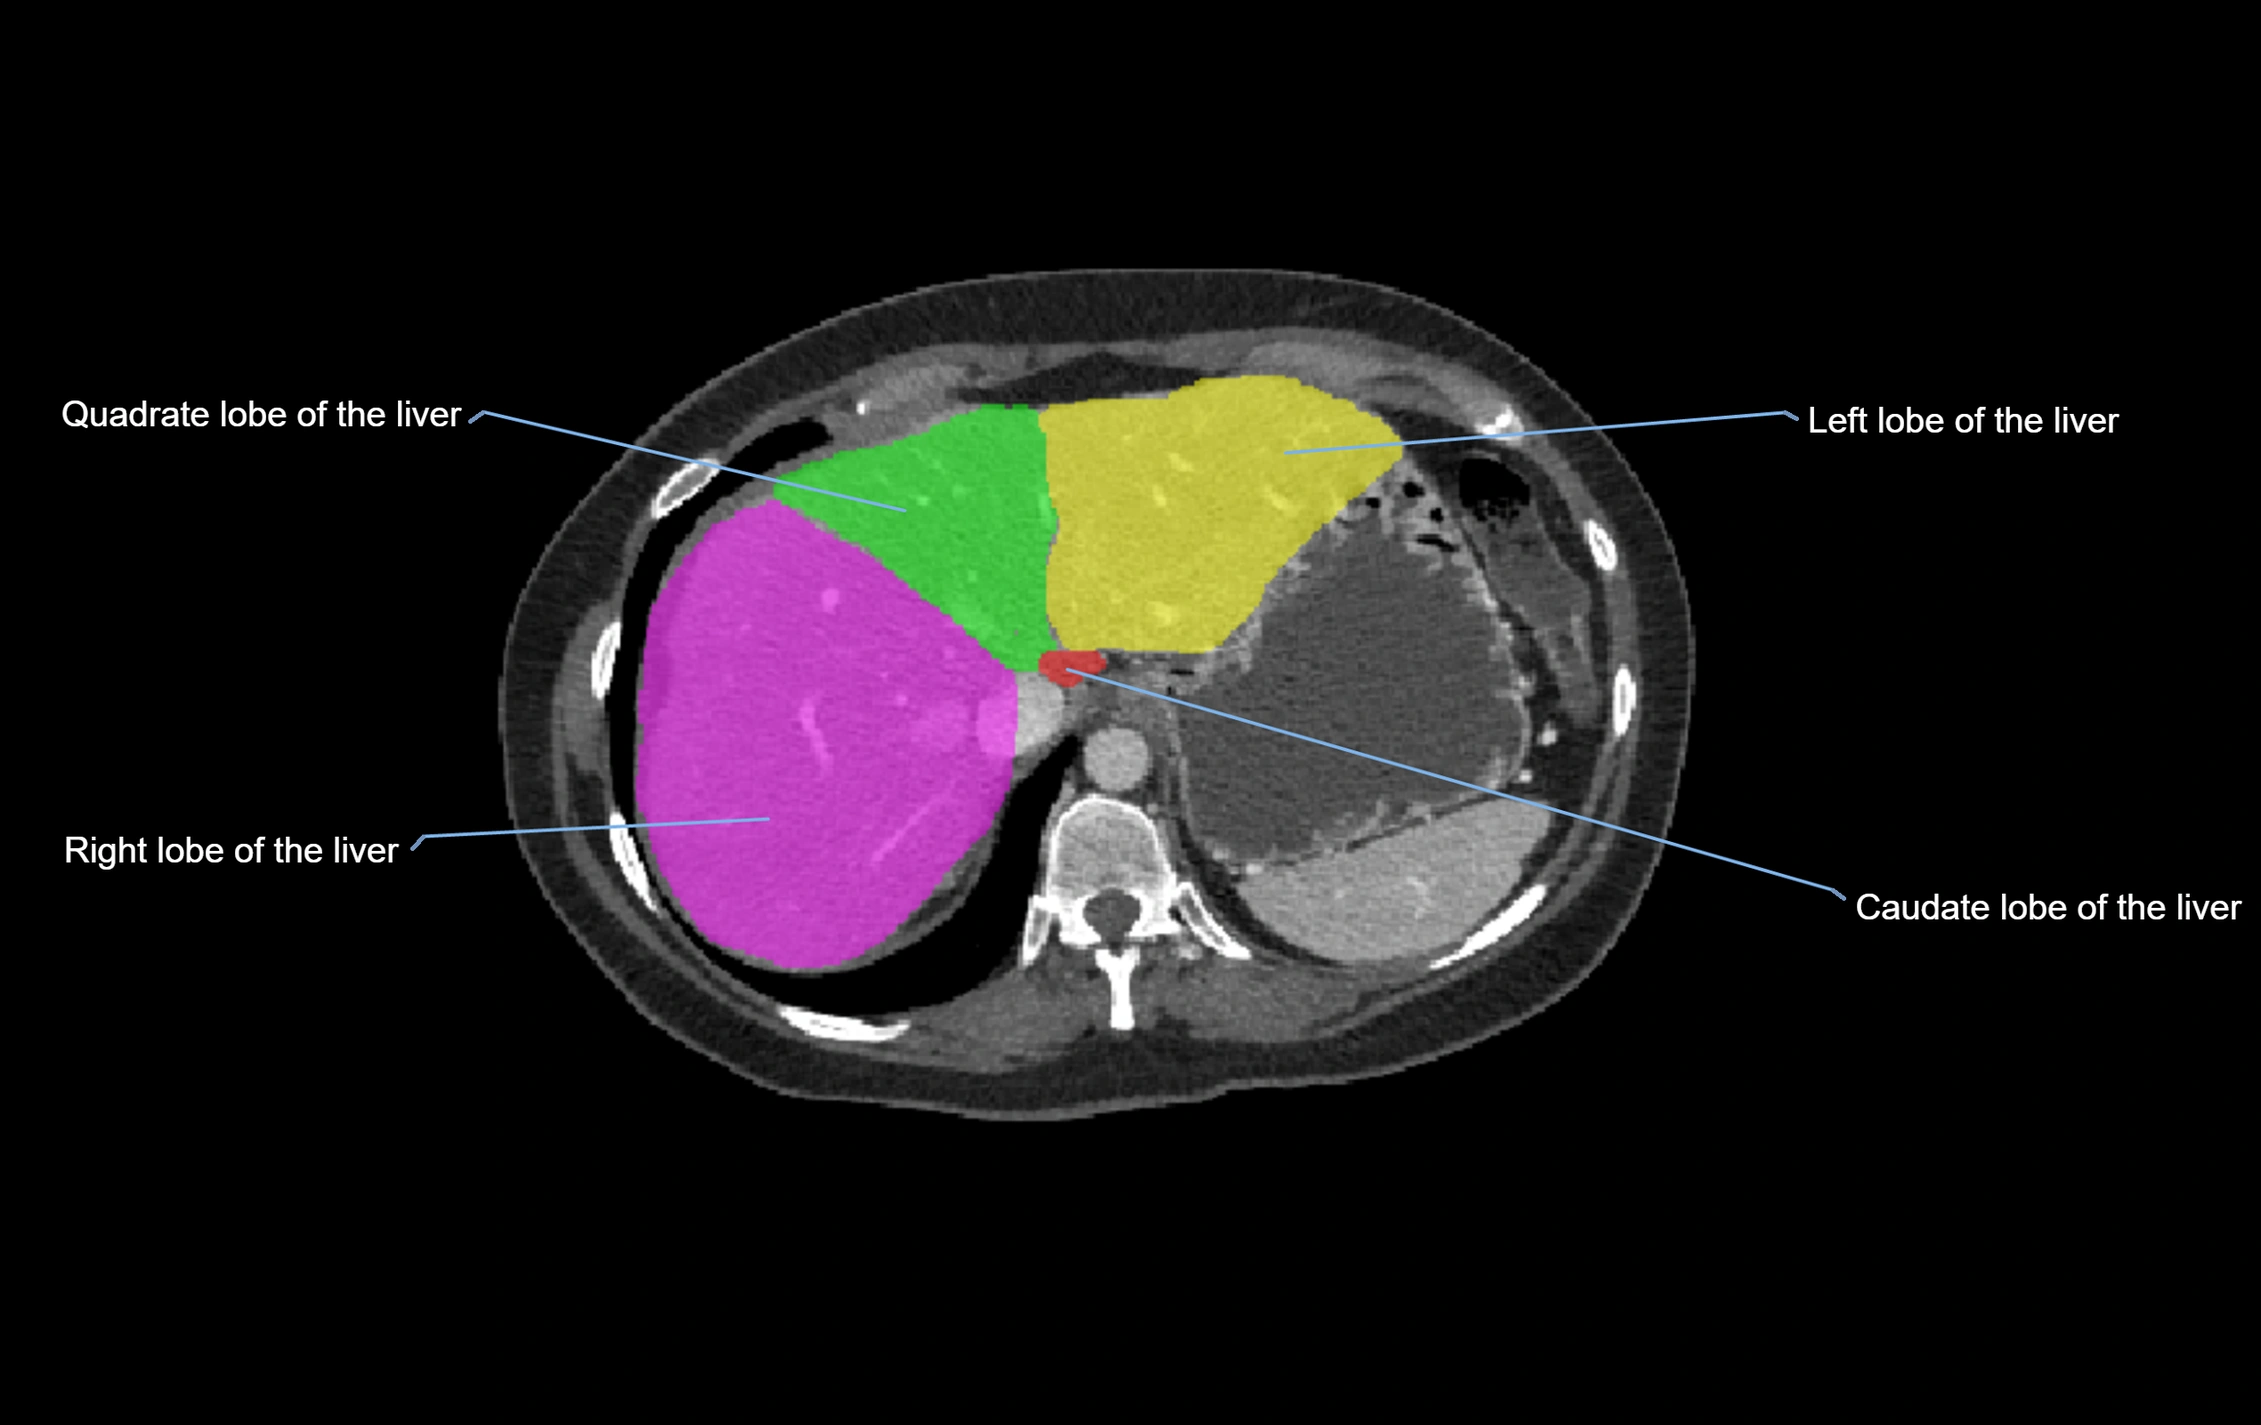

Caudate lobe of liver

The caudate lobe of the liver is a distinct anatomical subdivision of the liver, designated as segment I in Couinaud’s classification. It lies on the posterior surface of the liver, between the fissure for the ligamentum venosum (left boundary) and the groove for the inferior vena cava (IVC) (right boundary). Superiorly, it is related to the posterior liver surface, and inferiorly it is separated from the left lobe by the porta hepatis.

CT Appearance

CT Pre-Contrast:

• Caudate lobe appears as a soft-tissue density, isodense to the rest of the liver

• Enlargement may be appreciated in cirrhosis or Budd–Chiari syndrome

CT Post-Contrast:

• Homogeneous enhancement in the portal venous phase, similar to rest of liver

• Independent venous drainage into the IVC may be visualized

CT Image

image